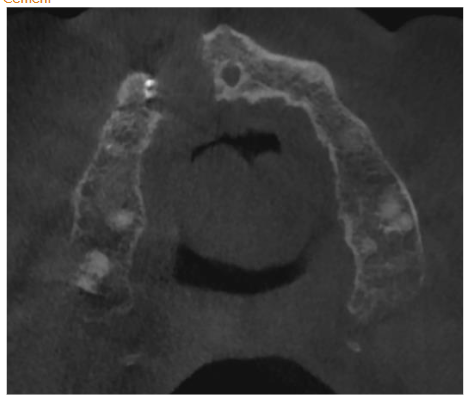

CBCT horizontal. Visible damage of buccal and palatal plate